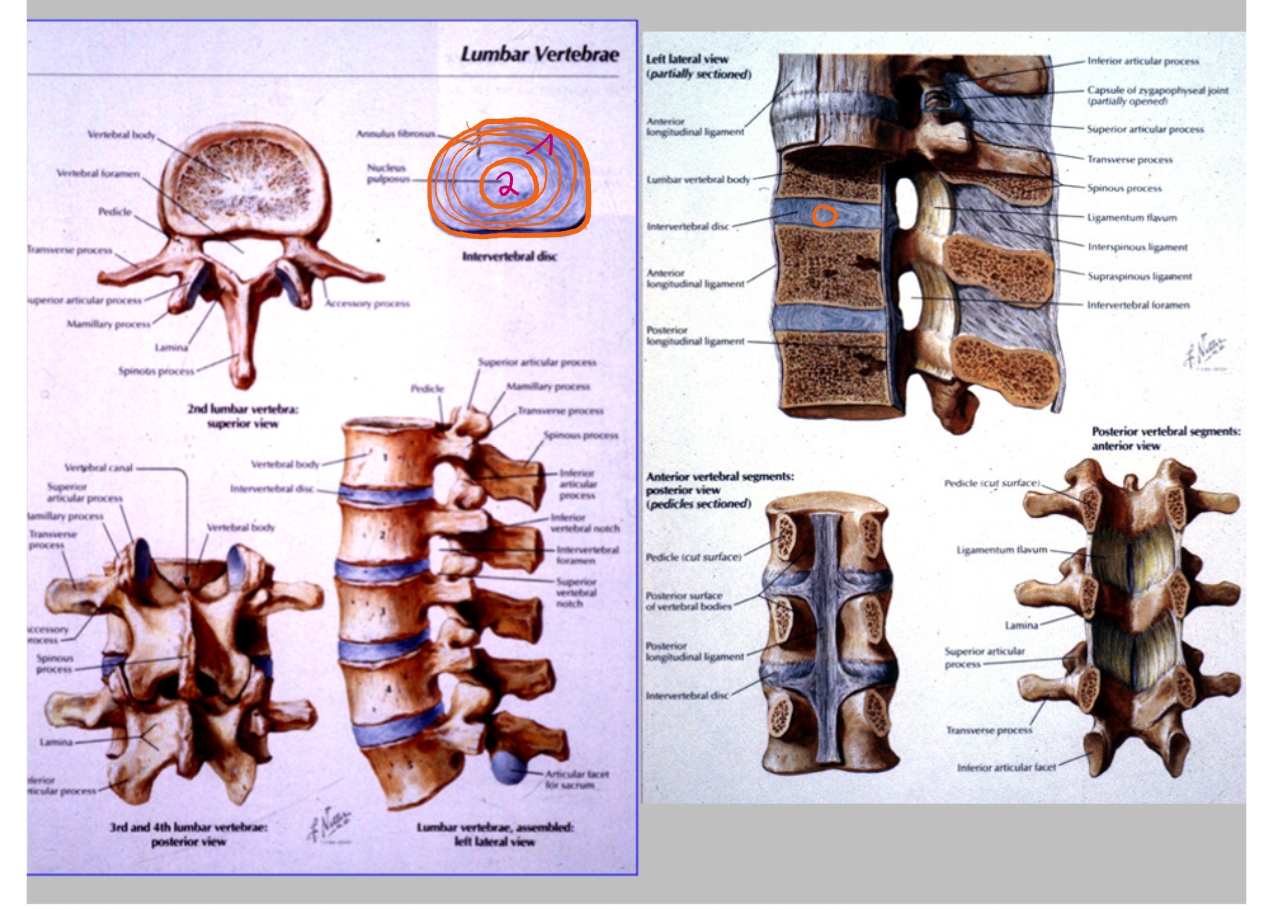

annulus fibrosus

buitenste vezels

vangt de krachten op

nucleus pulposus

enige wat nog overblijft van de embryologische chorda

corpus T12

rib 12

zwevende rib

bovenrand van de arcus

processus spinosus

processus articularis inferior

pedikel

corpus L3

processus transversus (links)

ala van het sacrum (= de vleugels)

corpus S1

vetlijntje op de psoas-spier

rib 12

ribben niet perfect op elkaar want patiënt is een beetje gedraaid

corpus L3

pedikel

processus articularis superior

processus articularis inferior

processus spinosus

discus intervertebralis

spinale zenuw L2

foramen intervertebrale

sacrum